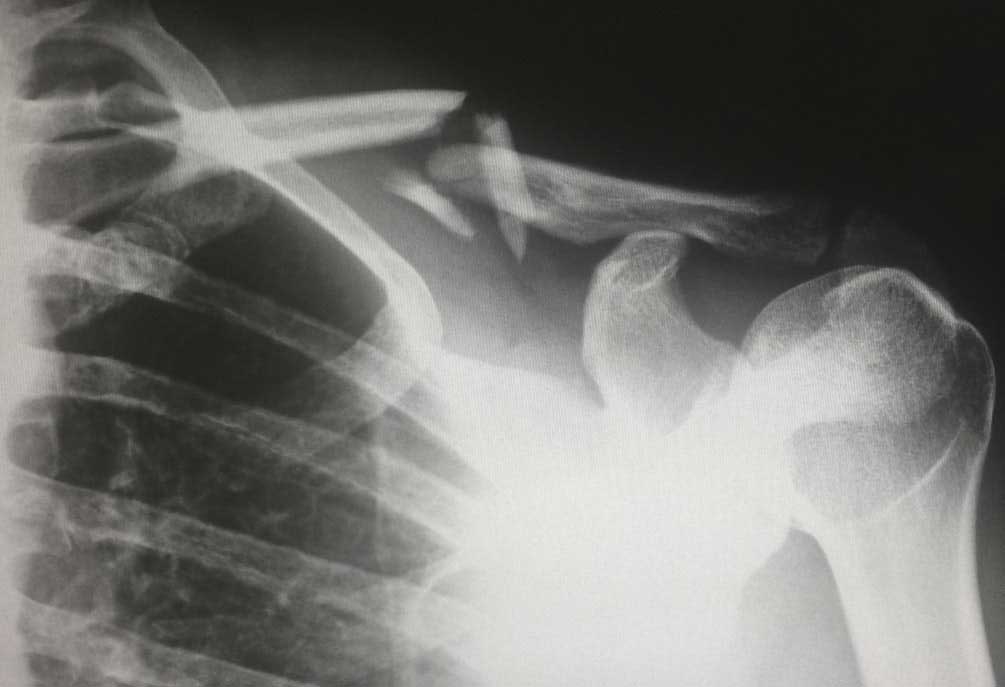

Hier is een lijst met. Artsen gebruiken gips spalken pinnen of andere hulpmiddelen om een fractuur in de juiste positie te houden tijdens het genezingsproces. Een botbreuk geneest via een aantal stadia waarbij het belangrijk is dat de uiteinden inderdaad op elkaar aansluiten middels een gips metalen plaat of een tuinstok.